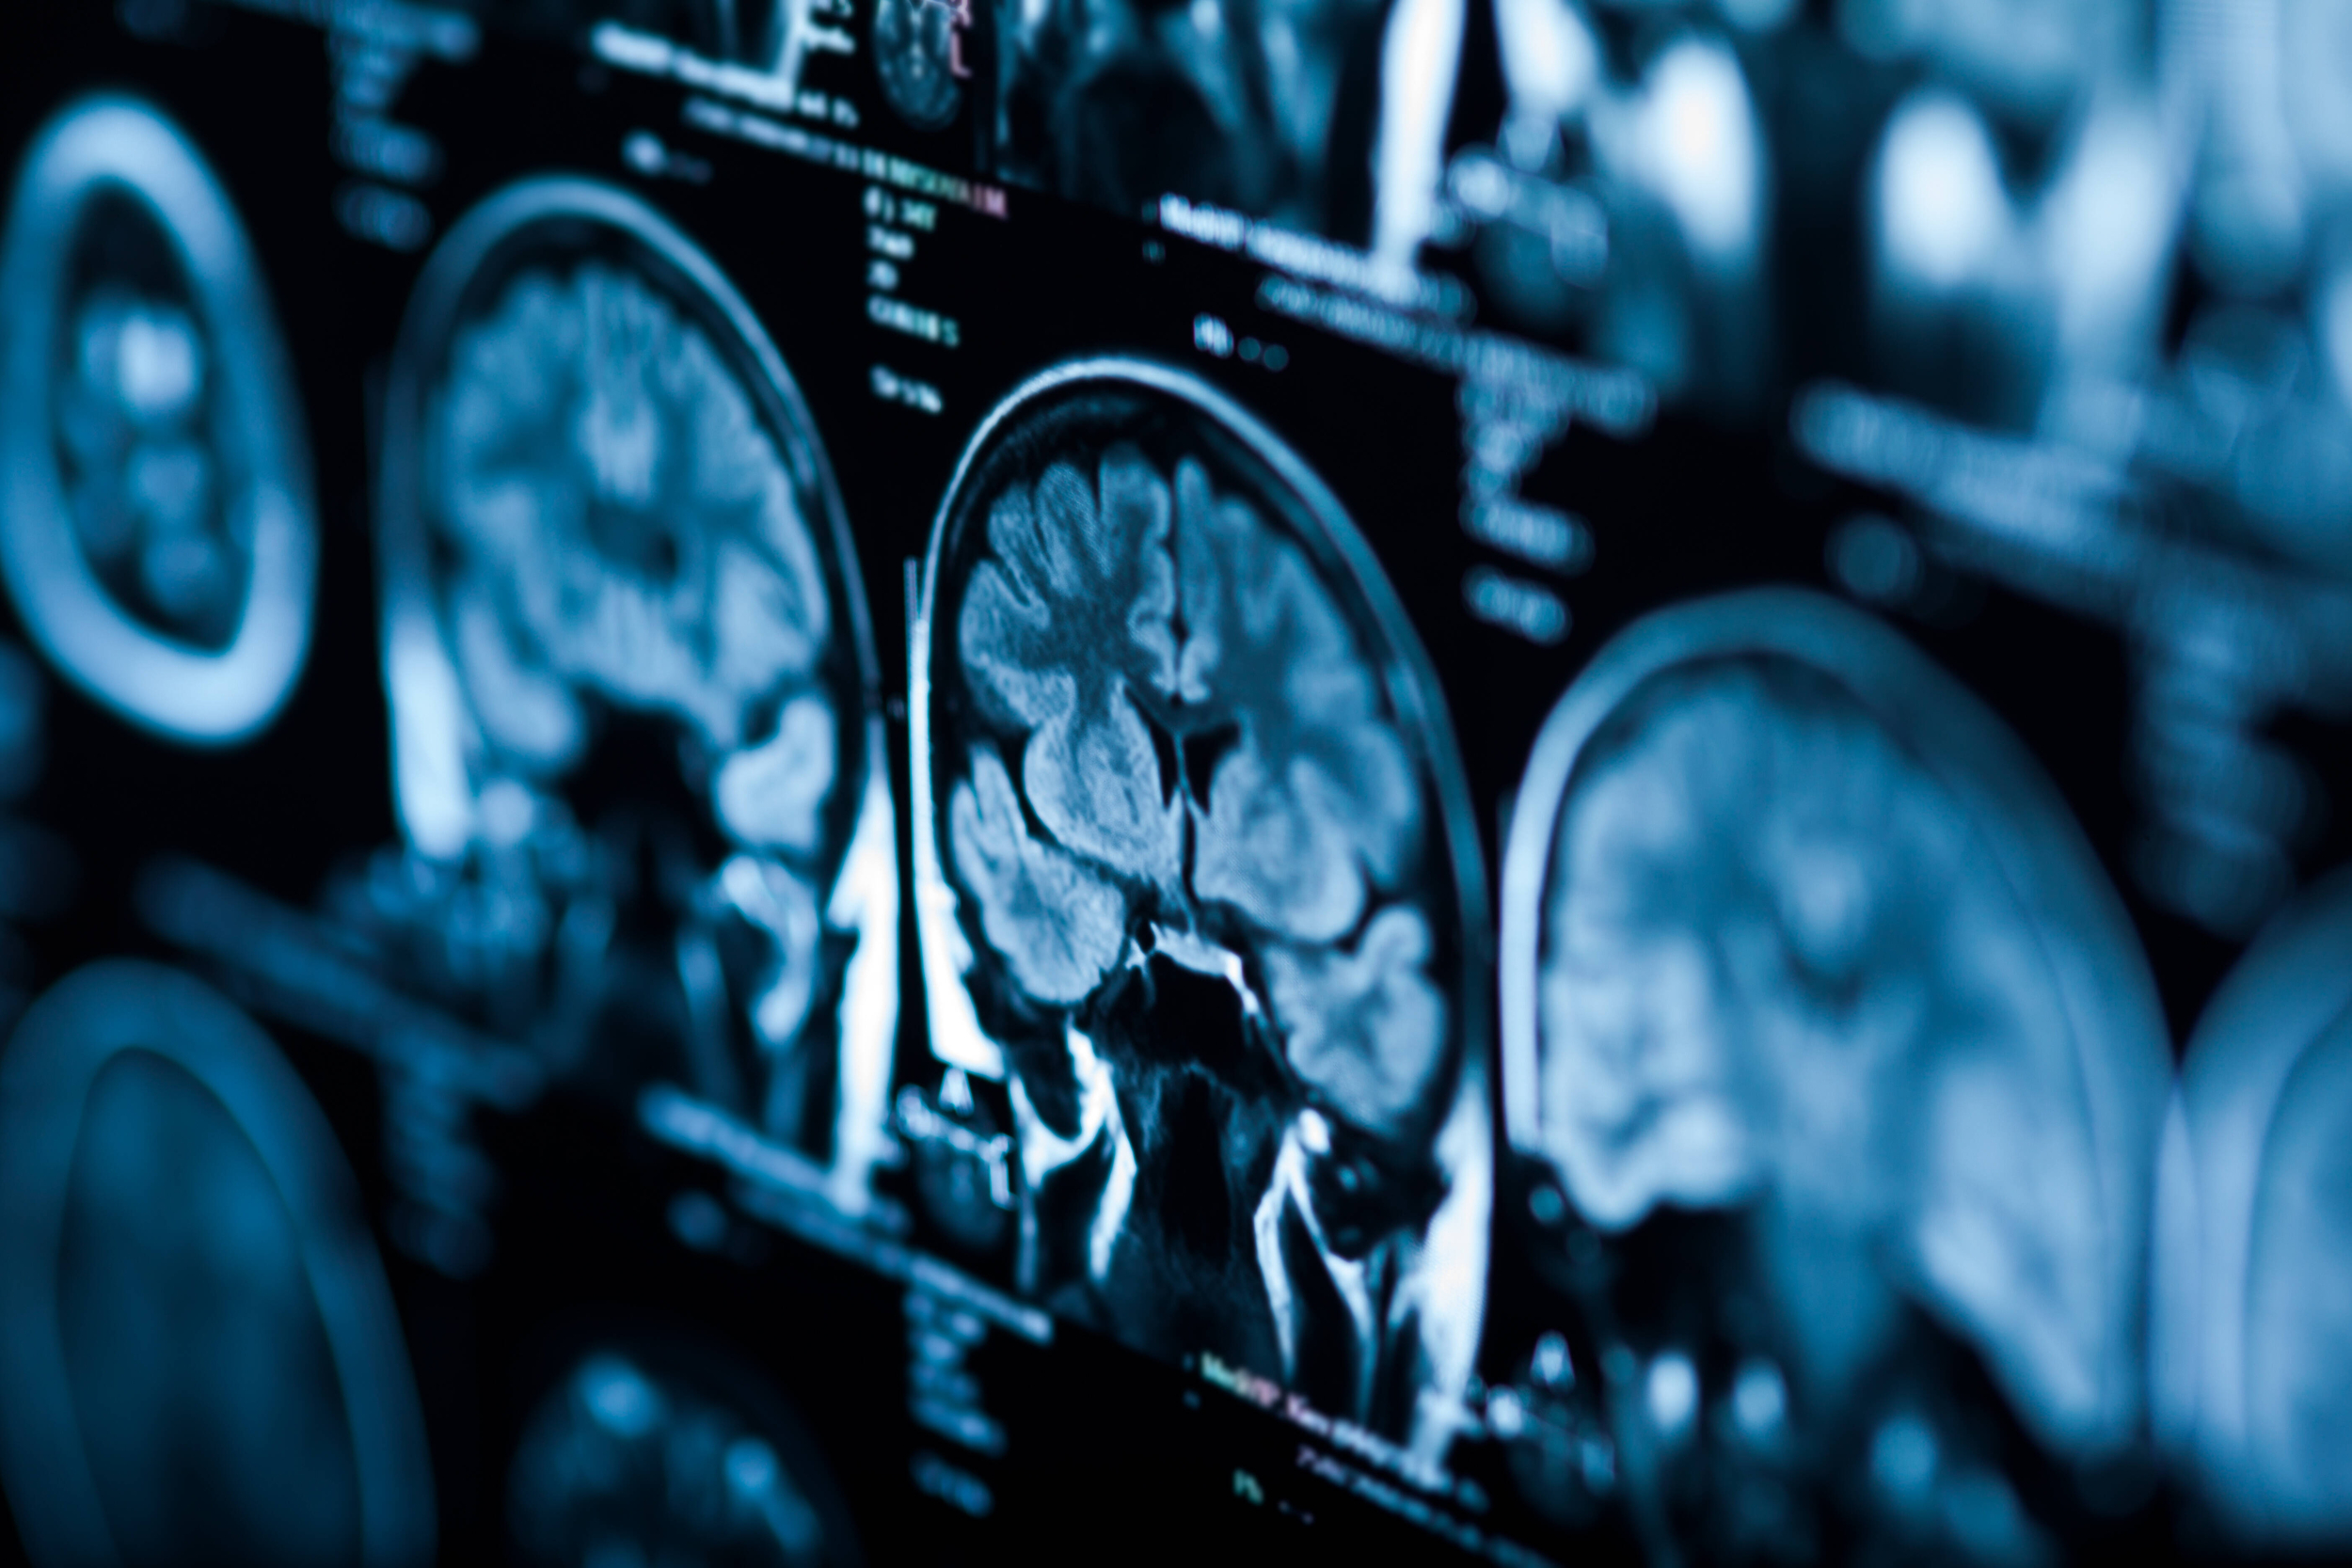

Tumori cerebrali e del distretto testa-collo: con l’intelligenza artificiale diagnosi più precise e veloci

Prosegue la collaborazione tra l’Università di Trento e l’Azienda provinciale per i servizi sanitari con una nuova alleanza nella diagnosi di importanti patologie. Questa volta al centro dell’attenzione è l’applicazione dell’intelligenza artificiale alla diagnosi dei tumori cerebrali – gliomi e meningiomi – e di quelli dell’area della testa e del collo. L’obiettivo rimane sempre quello di usare la tecnologia di ultima generazione per svolgere diagnosi più precise e veloci, meno invasive, pianificare in modo ottimale le terapie e, di conseguenza, migliorare le aspettative di vita e le condizioni generali dei pazienti.

Impiegare l’intelligenza artificiale al posto delle normali procedure di diagnosi ha un vantaggio importante. Le tecniche di analisi, in particolare, permettono di analizzare velocemente e senza procedure invasive informazioni quantitative e qualitative del tumore, peraltro non sempre rilevabili tramite la tradizionale osservazione visiva. Le immagini mediche, acquisite mediante risonanza magnetica, TC o PET, vengono convertite tramite algoritmi in dati numerici. Si tratta di una quantità elevata di dati da analizzare: un ambito ideale in cui trovano applicazione le tecniche statistiche dell’intelligenza artificiale. Con il computer vengono estratte numerose caratteristiche morfologiche specifiche del tumore (forma, volume, struttura tissutale) che possono essere associate alle caratteristiche molecolari e genomiche della stessa lesione. Questa analisi permetterà di valutare nel dettaglio il rischio clinico, predire con maggiore precisione l’aggressività del tumore e, di conseguenza, selezionare le terapie più indicate.

La sperimentazione della diagnosi tramite intelligenza artificiale partirà su alcuni tumori cerebrali (gliomi e meningiomi) e del distretto testa-collo. In questi tipi di tumore la diagnosi precoce è fondamentale: se trattati in anticipo e se le dimensioni sono ridotte, ci sono infatti buone speranze di guarigione. Se invece il tumore è di grandi dimensioni, la prognosi sarà peggiore e sarà necessario un trattamento prolungato e sicuramente più invasivo. L’intelligenza artificiale va così a supportare il lavoro di diagnosi da parte dei neuroradiologi e quello di pianificazione dell’intervento a beneficio di oncologi e neurochirurghi. La stessa tecnologia permetterà poi di seguire l’evoluzione clinica nel paziente attraverso dispositivi non invasivi per il monitoraggio dei parametri vitali.